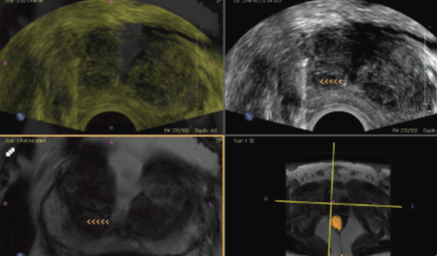

Philips Fusao E Orientacao Fusao De Imagens E Orientacao De Agulha

Fusao Entre Imagens De Ultrassom E Hospital Israelita Albert Einstein Facebook

Fusao De Imagens Vero Dellaudo